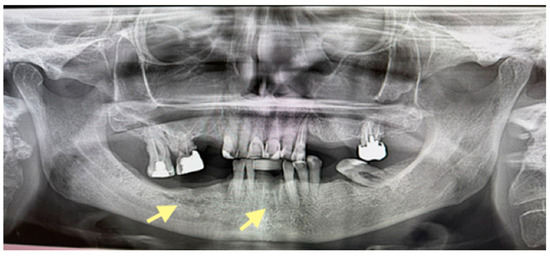

Figure 4.

OPG (orthopantomogram) before surgery (12 January 2024). In the fourth quadrant, we do not see any changes, which are typical in the initial stages of osteonecrosis.

Figure 5.

OPG (orthopantomogram) performed on 21.08.2024.